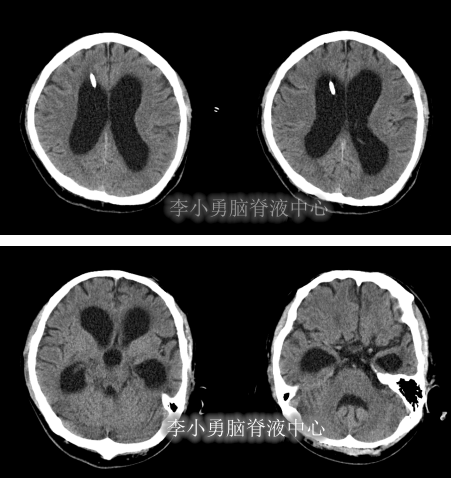

2012年9月11日,入院时:神志模糊,反应迟缓。头颅额部右侧手术瘢痕,双眼睑轻度浮肿,左眼眶凹陷,两侧瞳孔对光反射右侧存在,左侧消失,大小便失禁,体温高达39.5°C,发病以来体型消瘦,不能遵嘱活动,刺痛后四肢有反应但无发声,不能言语,饮食差,四肢肌张力增高,左上肢肌屈曲强直,余肢体肢活动受限,肌力3级(图-13),头部CT示脑干弥漫性皱缩损伤后,脑积水(图-14)。

图-13:2012年9月11日入院时

图-14:2012年9月11日头部CT

脑室外引流术后12天即2012年9月24日,患者体温连续1周正常,意识模糊好转为了嗜睡。查头部CT示脑室外引流术状态(图-15)。

图-15:2012年9月24日头部CT